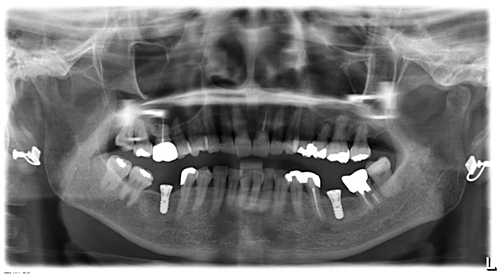

術前のレントゲン写真です

歯周病や虫歯など細菌感染による疾病は原則的に術前に治していますので、悪い歯を取った後のように腫れることは少ないです。

術後のレントゲン写真です

下の奥歯にインプラントが良い状態で入りました。

次回来院時に型取りをして綺麗でしっかり噛める歯が入ります。